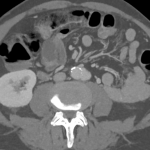

Saccular aortic aneurysm

60 year old male patient presented to the hospital with severe pain in the adbomen.He underwent a CT scan which...